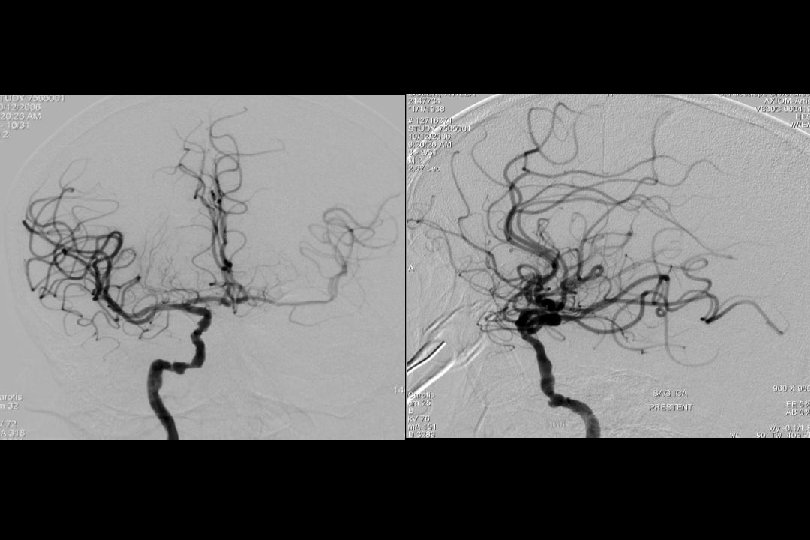

71 y kadın hasta En iyi medikal tedavi altında post fossa iskemik ataklara neden olan baziler stenoz

Sağ brakial yaklaşım ile Reflex /Navien servikal R- VA’e ve intrakraniyal segmente ilerletilmiştir.

PTA sonrası

. . 6 mm Solitaire ile Stentleme sonrası